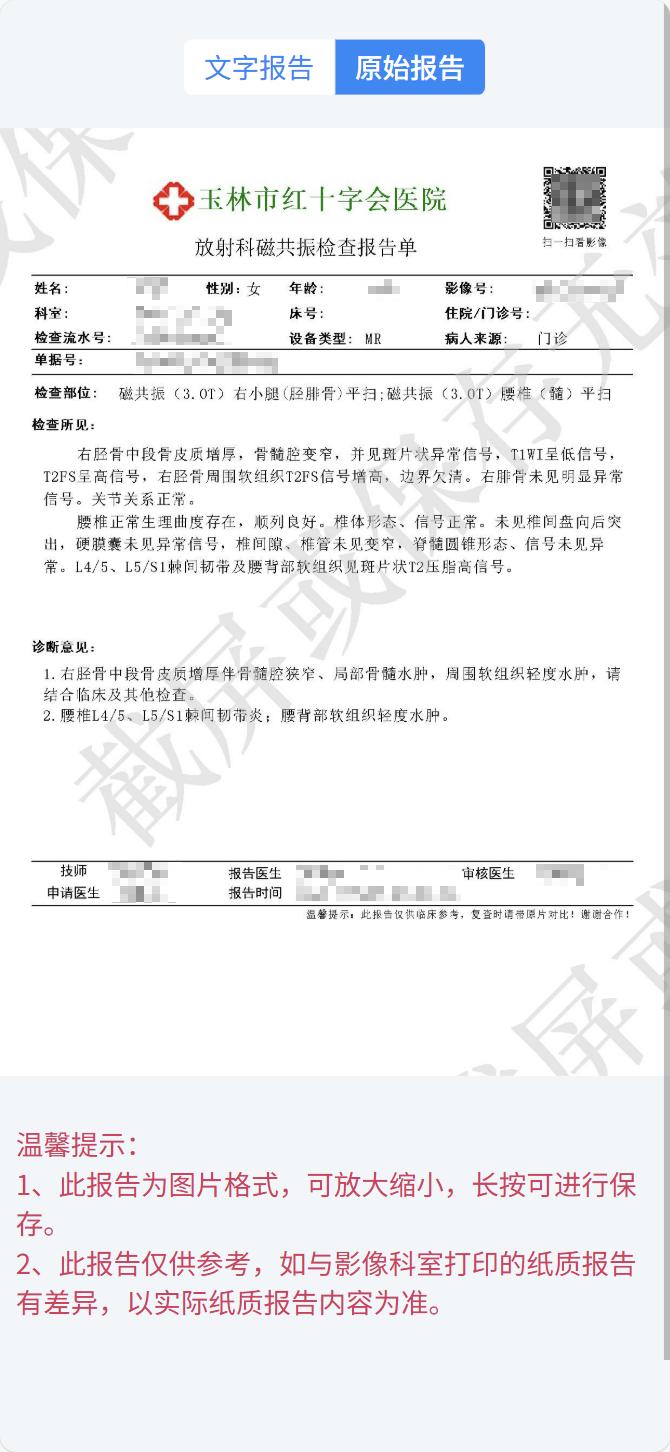

方式一:扫描检查报告单右上角二维码

拿到报告单,扫描二维码,输入手机后四位或身份证后六位(隐私保护,妥妥的~),就能轻松解锁你的“电子影像大礼包”!

如下图所示:

点击“报告单”和“查看影像”分别查看检查报告单及检查电子影像;